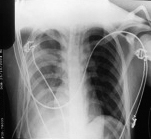

Requirió una segunda punción y drenaje a las 24 hs de la primera, por persistencia del derrame en radiografía de control y con sintomatología de dificultad respiratoria. (Figura 2)